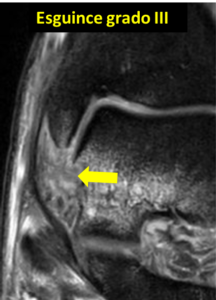

Grados de lesión del esguince de tobillo

Los esguinces de tobillo se clasifican en tres grados distintos en función de la severidad de la lesión.

-Grado I: Distensión de los ligamentos: Este es el grado menos grave de lesión, la torcedura provoca una elongación de las fibras del ligamento, aunque no existe rotura. El tejido alrededor del ligamento se inflama, lo que contribuye a aumentar el dolor y la movilidad del tobillo se ve afectada por el dolor, al menos de forma parcial. Habitualmente el tiempo de recuperación se sitúa entre 2 y 4 semanas.

-Grado II: Rotura parcial: La rotura parcial es el siguiente grado de severidad, la inflamación y el dolor son mayores y puede aparecer hematoma en la piel por la rotura de algunas fibras de los ligamentos, aunque el ligamento sigue teniendo fibras que no se encuentran dañadas. El tiempo de reposo suele estar entre 4 y 6 semanas.

-Grado III: Rotura completa: El ligamento se rompe completamente, por lo que la estabilidad del tobillo estará comprometida hasta que sane. El tiempo de recuperación se puede demorar entre 6 y 8 semanas. Es el grado más grave de lesión y ocasionalmente puede requerir cirugía si la inestabilidad persiste tras el tratamiento conservador.

Para diagnosticar adecuadamente un esguince y determinar su tratamiento correcto basta con realizar una exploración física adecuada y en los casos que sospechamos una lesión ósea hacer unas radiografías que descarten una fractura. Dado que el tratamiento inicial como luego veremos está determinado por la exploración física e inicialmente siempre es conservador, habitualmente el resto de pruebas complementarias (ecografía o resonancia magnética) se indican cuando la evolución no es adecuada a lo largo del tiempo o se sospechan lesiones asociadas.